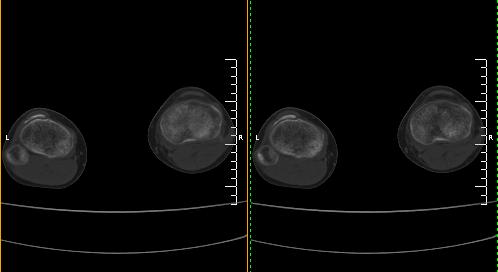

标题: CT19091:右胫骨近段骨性突出.

男,15岁,右胫骨近段软组织肿胀,下肢疼痛10左右.

右胫骨近端内侧骨性突起,皮质连续,骨质结构正常,首先考虑胫骨骨软骨瘤,随访观察。